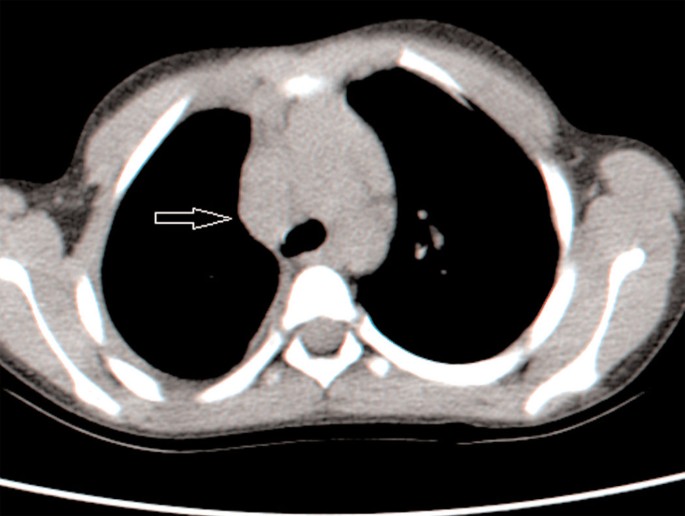

Her asymptomatic 7-year-old daughter had a positive 22mm TST and her CXR revealed a loculated right pleural effusion (Figure 2). She was admitted to the paediatric ward for further investigation. A diagnostic thoracentesis was performed but only a small amount of exudative pleural fluid was drained, with a leucocyte count of 1800/μl, predominantly (60%) lymphocytes. Because of the small amount of pleural fluid drained, TB culture and measurement of adenosine deaminase levels could not be performed. Sputum and gastric aspirate were collected for smear and TB culture. Chest computed tomography showed a loculated right pleural effusion (Figure 3) and mediastinal lymphadenopathy with no pulmonary parenchymal infiltrate (Figure 4). Treatment for TB was initiated with a four first-line drug regimen (INH, RIF, pyrazinamide (PZA), and EMB). The effusion eventually resolved without any sequelae. Cultures of her sputum and gastric aspirate were never positive.

While every effort should be made to attain bacteriological confirmation of disease including invasive procedures, in vulnerable populations treatment initiation should not be delayed by waiting for a definite diagnosis.16 In the case of the 7-year old-daughter, further investigations such as bronchoscopy or pleural biopsy were considered. However, on the basis of the epidemiological background, the low yield from bronchoscopy when no parenchymal lung involvement was evident on the chest computed tomographic scan, and the possible complications of pleural biopsy in a 7-year-old 20kg child, we proceeded with full anti-TB treatment while awaiting culture results.17